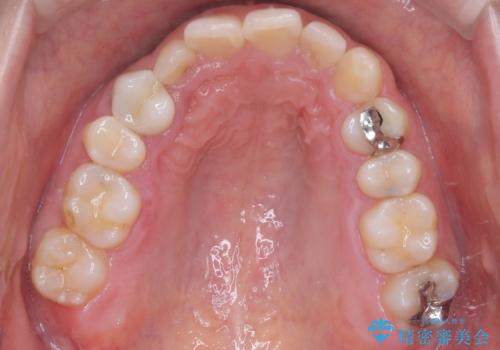

- 下の歯のがたつき(叢生)、真ん中(正中)が右にずれていることを主訴に来院されました。右上前から3番目の永久歯が埋まっている(埋伏)していることから正中は可能な限り合わせることをゴールとしてマウスピースでの矯正治療を選択しました。

今回の矯正治療では、透明なマウスピース型の装置インビザラインを使用しました。がたつきをとるため、安全性が確保できる範囲で歯と歯の間を少し削り必要なスペースを確保しました。